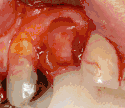

Long-term failures are due to either loss of bone around the tooth and/or gingiva due to peri-implantitis or a mechanical failure of the implant. Because there is no dental enamel on an implant, it does not fail due to cavities like natural teeth. While large-scale, long-term studies are scarce, several systematic reviews estimate the long-term (five to ten years) survival of dental implants at 93–98 percent depending on their clinical use.[2][3][4] During initial development of implant retained teeth, all crowns were attached to the teeth with screws, but more recent advancements have allowed placement of crowns on the abutments with dental cement (akin to placing a crown on a tooth). This has created the potential for cement, that escapes from under the crown during cementation to get caught in the gingiva and create a peri-implantitis (see picture below). While the complication can occur, there does not appear to be any additional peri-implantitis in cement-retained crowns compared to screw-retained crowns overall.[75] In compound implants (two stage implants), between the actual implant and the superstructure (abutment) are gaps and cavities into which bacteria can penetrate from the oral cavity. Later these bacteria will return into the adjacent tissue and can cause periimplantitis.